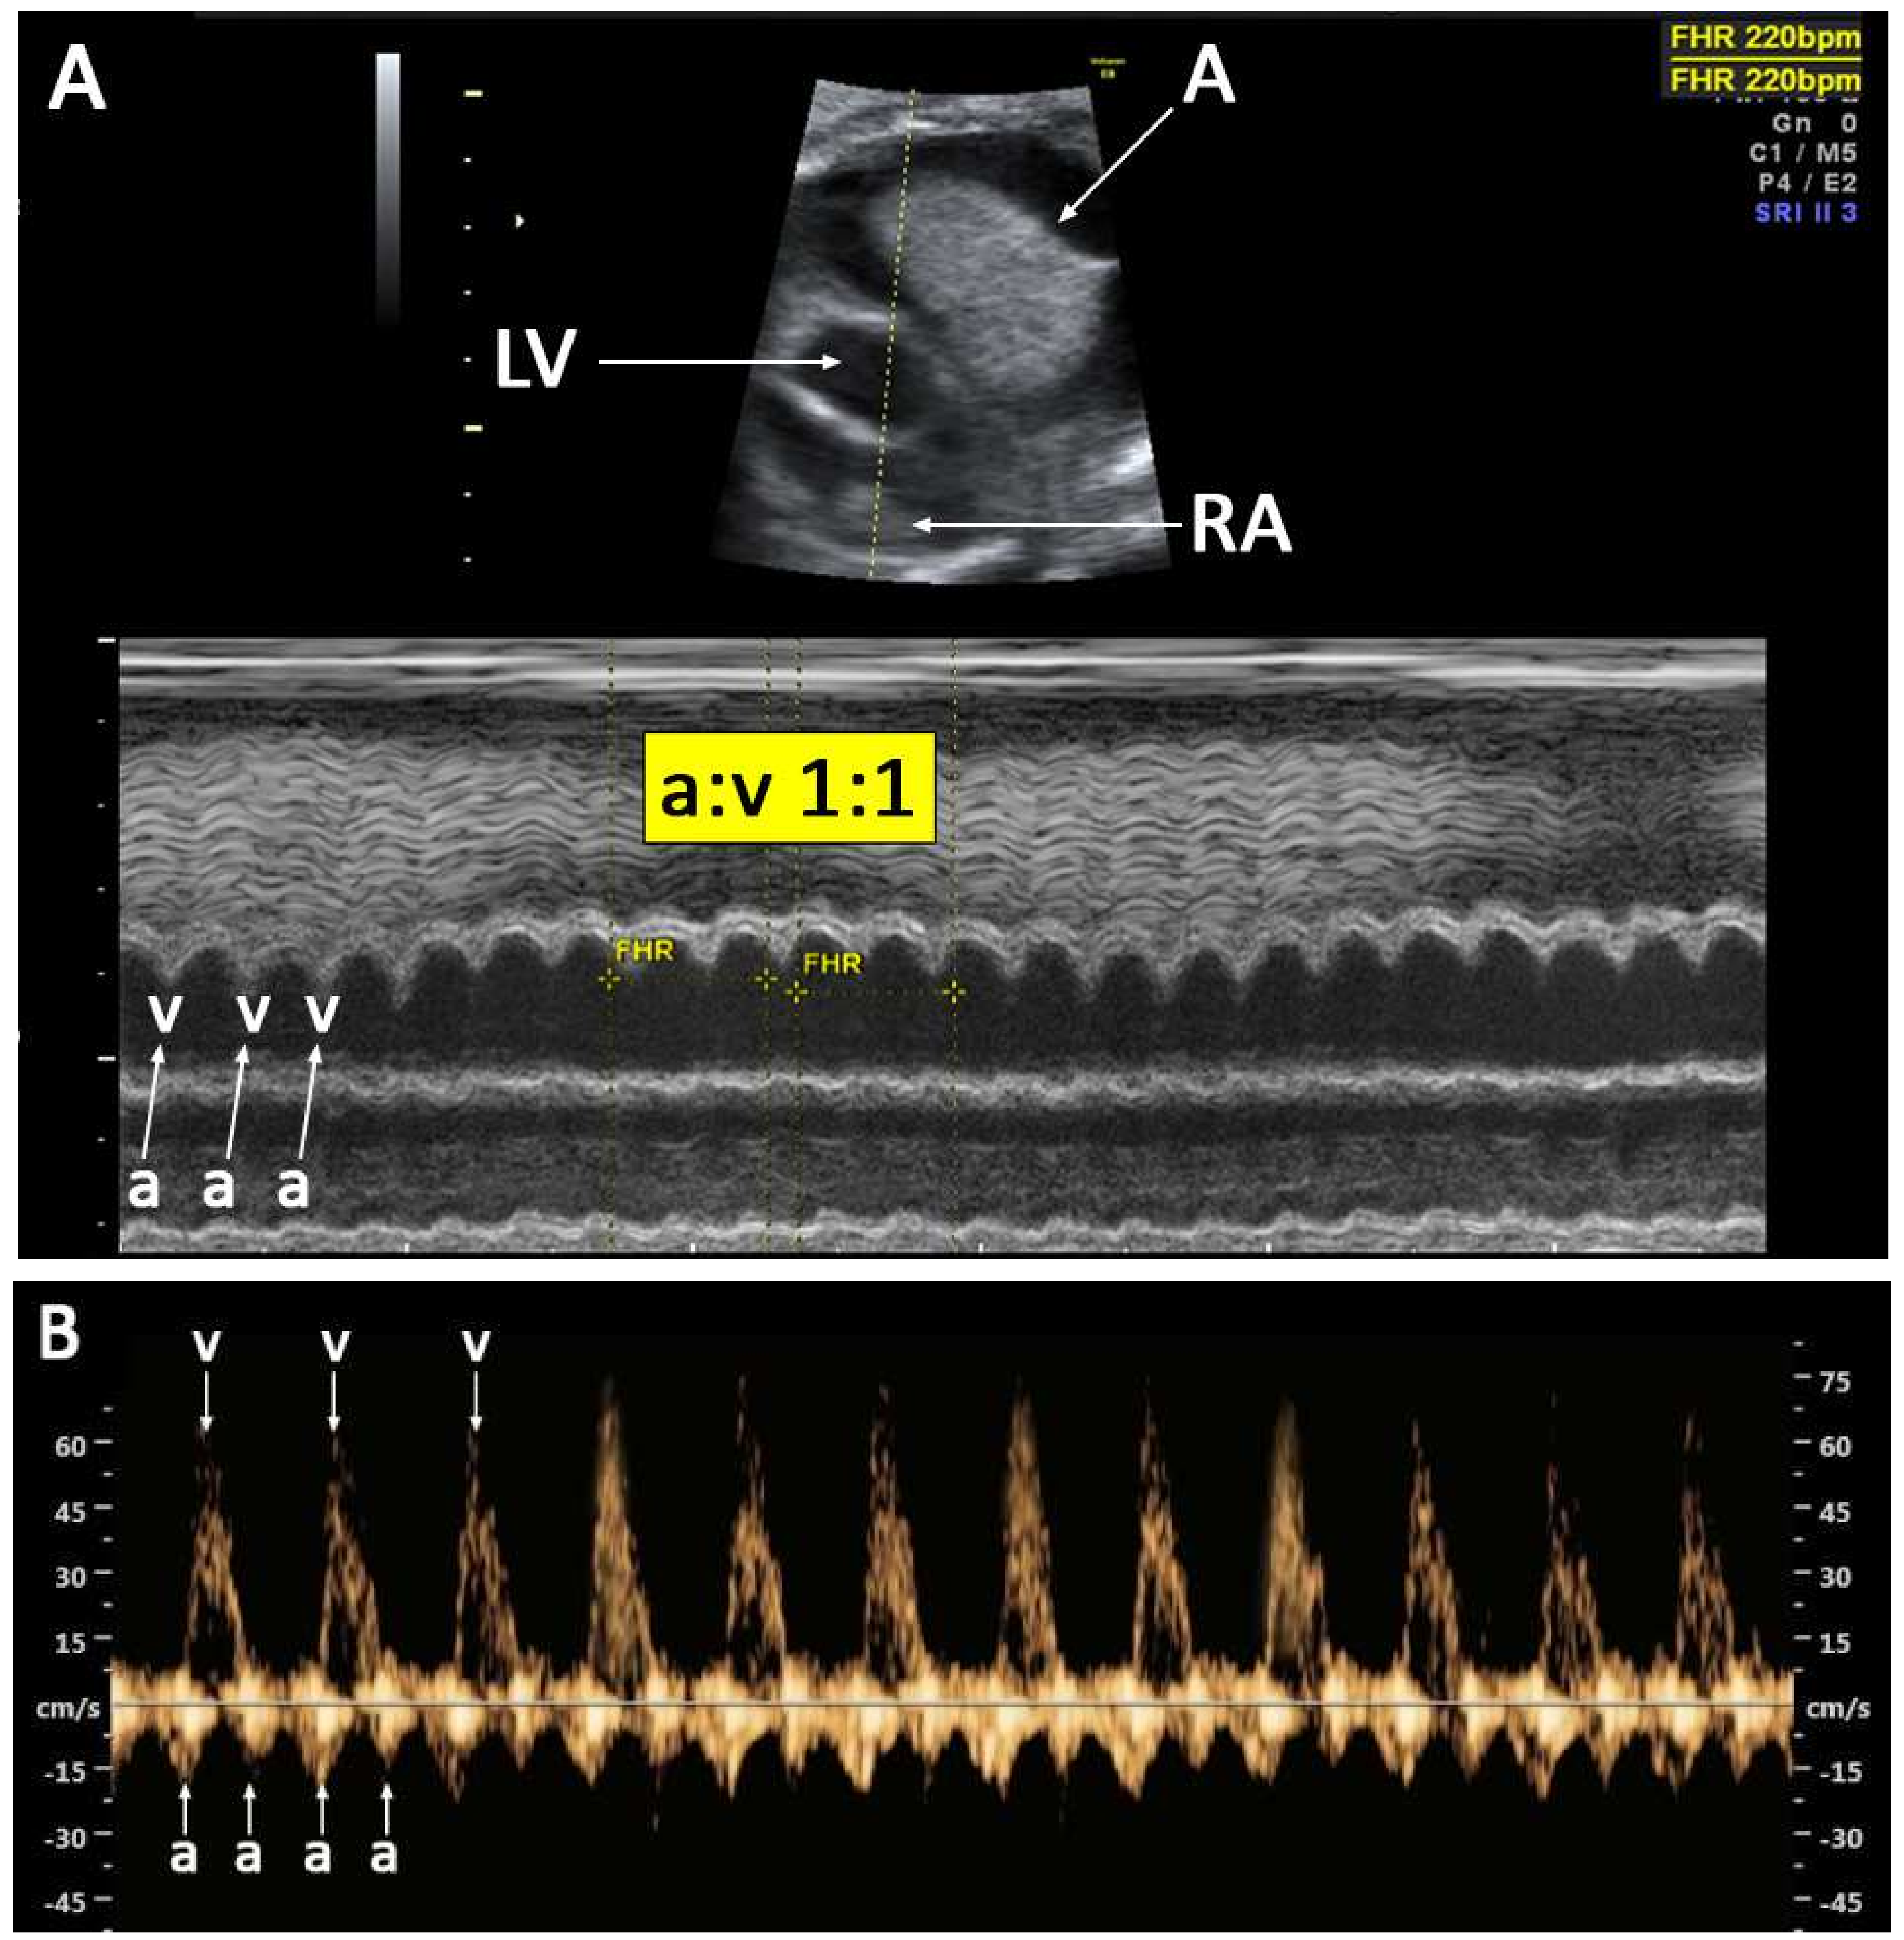

2. Case Series